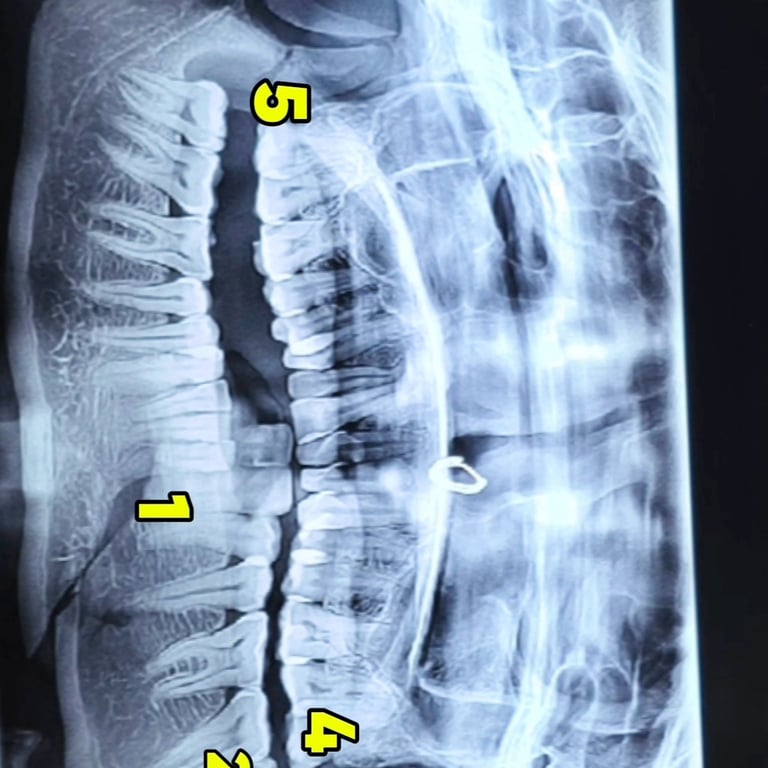

Facial trauma cases involving mandibular fractures are among the most common maxillofacial emergencies seen in dental and surgical practice. A fractured jaw not only causes severe pain and swelling but also affects chewing, speech, and overall facial aesthetics. In this blog, we present a rare case of multiple mandibular fractures in a 40-year-old female patient, including angle fracture, parasymphysis fracture, condylar fracture, and coronoid fracture—all treated successfully with intermaxillary fixation (IMF) and plating.